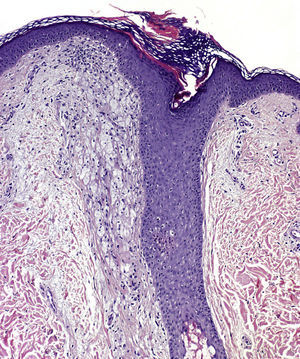

Histologic examination of a papule from the lower presternal region revealed dilatation and hyperkeratotic plugging of the follicular infundibulum, which was surrounded by abundant foamy histiocytes (xanthomized macrophages) (Fig. 2); a mild-to-moderate periadnexal chronic lymphocytic inflammatory response; and clusters of apocrine cells, with a tendency to cystic dilatation, between the reticular dermis and hypodermis (Fig. 3).

The defining histopathologic features of FFD vary widely. Descriptions include dilatation and hyperkeratosis of the follicular infundibulum, spongiosis and dyskeratosis of the infundibular epithelium, vacuolar degeneration of the dermoepidermal junction, presence of periadnexal inflammatory lymphocytic infiltrate, parakeratosis of the infundibular epithelium in the form of cornoid lamellae, dilatation of the apocrine glands, and perifollicular xanthomatosis. The last is considered among the most characteristic findings.3,8,9